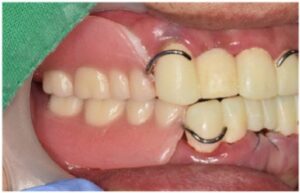

모든 치료가 마무리된

구강 내 사진과

파노라마 사진인데요.

환자분께서는

그동안 앞니로 식사하시면서

불편감이 많으셨는데

치료 후 양측 저작이 편안하게 잘 되고

전보다 심미적으로 변한 모습에

만족해하셨습니다.

양측 어금니 보철물에 맞춰

위아래 앞니 브릿지 보철물도

같이 제작을 도와드렸으며,

최종 보철물은

자연치아와 강도가 유사하고

심미적인 지르코니아로

마무리해 드렸습니다.